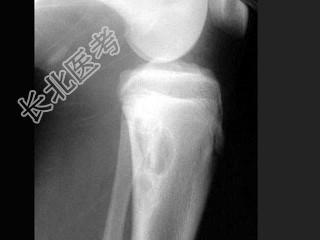

- 单项选择题男,22岁, 膝部酸痛、肿胀,结合图像, 最可能的诊断是 ( )

A、纤维性骨皮质缺损

B、嗜酸性肉芽肿

C、非骨化性纤维瘤

D、软骨黏液样纤维瘤

E、骨样骨瘤